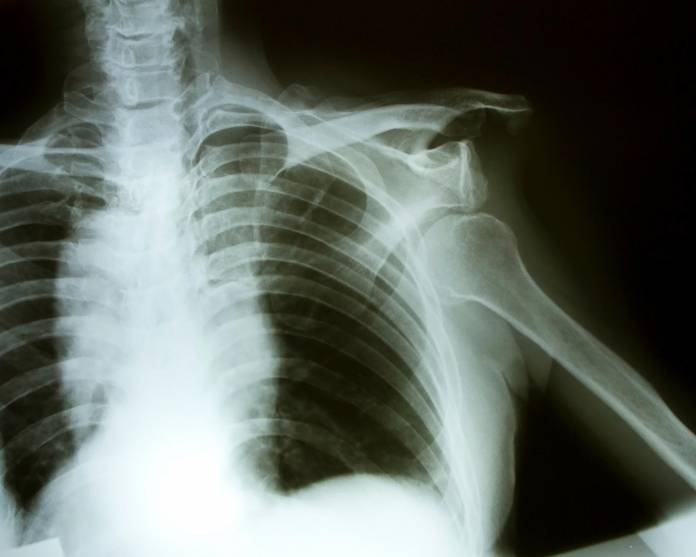

Mit Röntgenaufnahmen kann eine Schulterluxation bildlich dargestellt werden, außerdem können Knochenverletzungen am Oberarm oder der Gelenkpfanne erkannt werden. Nur in Ausnahmefällen, wenn eine Schulterluxation mittels Röntgenaufnahme nicht eindeutig festgestellt werden kann oder wenn ein Verdacht auf eine Verletzung der Muskulatur, von Knorpel- oder Kapselgewebe besteht, wird gegebenenfalls eine Kernspintomographie (MRT) durchgeführt.